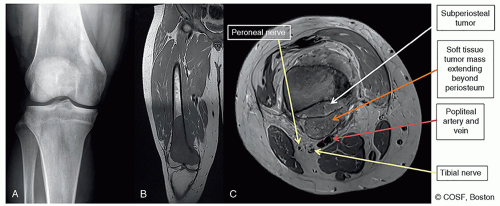

Surgical Approach (Figure 42.3)

Length of incision from below tibial tubercle to 2 to 5 cm proximal to planned bone cut (depending on thickness of soft tissue envelope) (Figure 42.4)